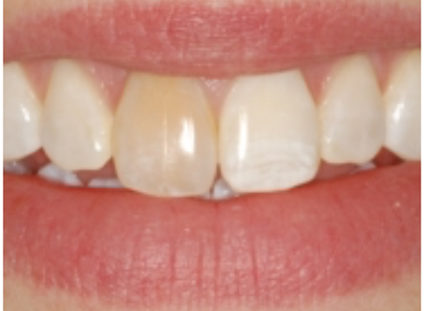

Figure 1: Pulp canal obliteration (PCO). The patient had trauma to UL1 15 years ago and developed a yellow discolouration over time. She was keen to improve the appearance of the tooth. The UL1 was asymptomatic and did not respond to sensibility testing.

Radiographically, UL1 had a normal PDL width and an intact lamina dura could be seen around the tooth. A diagnosis of pulp canal obliteration was reached for UL1. There was no endodontic infection and the patient was advised to have external tooth whitening; this will take longer and a veneer might be necessary if a satisfactory result can’t be achieved with external whitening alone. Figure 1a: Preoperative photograph. Figure 1b: Preoperative radiograph.